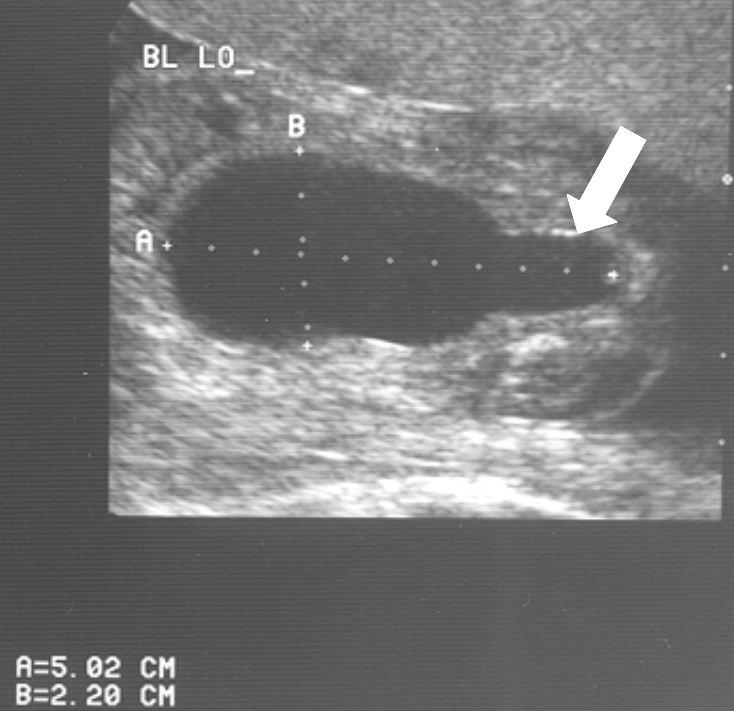

Diagnose vóór de geboorte

Veel ernstige vormen van urethrakleppen worden al gezien bij echografisch onderzoek vóór de geboorte. Bij de 20 weken echo (of misschien in de toekomst bij een 13 weken echo) worden verwijde nierbekkens en urineleiders gezien. De blaas kan dikwandig zijn, maar ook zeer groot en uitgerekt. Vaak kan het verwijde deel van de plasbuis ónder de blaas worden gezien. Dat noemen we het “sleutelgat teken” omdat de blaas in lengtedoorsnede op de echo er dan uitziet als een sleutelgat. De hoeveelheid vruchtwater kan normaal of verminderd zijn. Als er een verdenking is op urethrakleppen wordt de bevalling gedaan in een centrum waar direct optimale zorg kan worden geleverd aan de pasgeborene.

20 weken echografie: links: dikwandige blaas met verwijding van de plasbuis tot aan de kleppen (pijl): het “sleutelgat teken”. Onder: verwijde urineleiders. Bij kinderen gaan de urineleiders bij verwijding ook erg gekronkeld verlopen.

Verwijde nierbekkens (lange pijl) en nierkelkjes (korte pijl). Smalle nierschors.